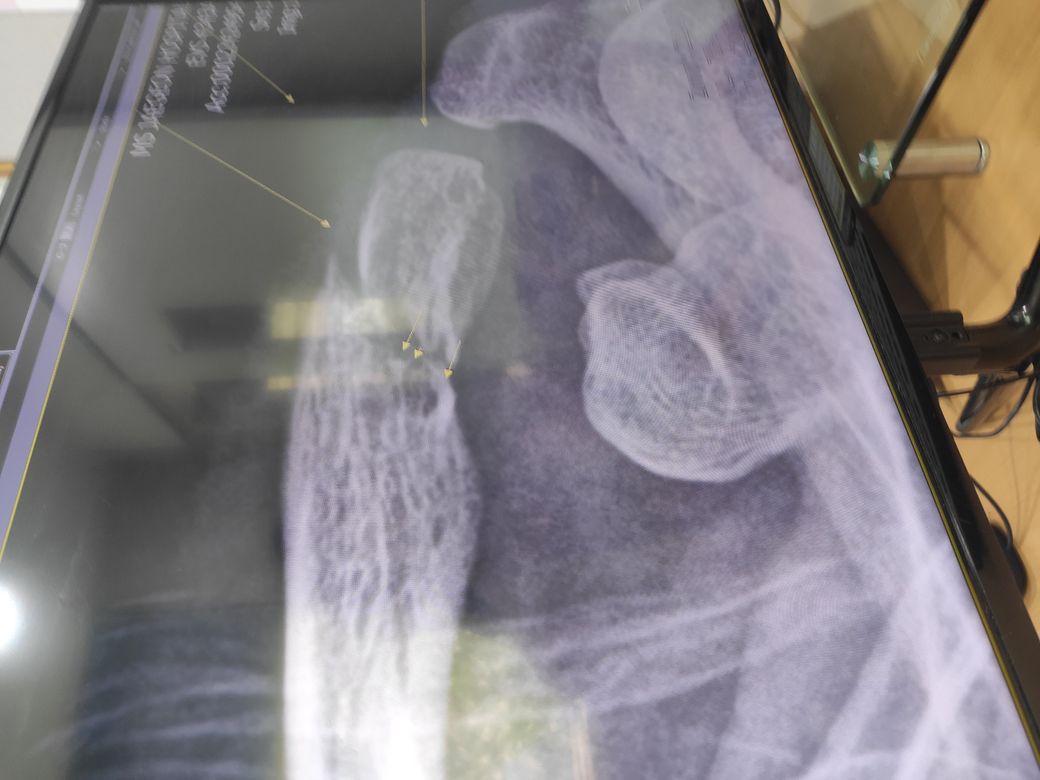

사진 보기에 어떻습니까

X-ray 한장만으로 정확한 평가가 어렵지만 쇄골의 골절이 명확한 것으로 보이며 수술을 반드시 할 필요는 없습니다.

현재 골절편의 전위가 심하지는 않아 꼭 수술을 하셔야 하는 것은 아닙니다.

쇄골이 많이 움직이는 부위가 아니라고 하시긴 하였지만 팔의 움직임에도 영향을 받으며, 특히 골절된 부위가 바깥쪽인 만큼 움직임이 적다고도 할 수 없는 부위이긴 합니다. 올리신 엑스레이 한 장 만으로 확실하게 결정하긴 어렵지만 사진의 소견만으로 볼 때에는 변형이 심하지 않아 잘 붙으면 수술적 치료 없이도 회복이 가능할 수 있을 것 같습니다. 하지만 회복이 잘 안 될 수도 있기 때문에 결국 결정은 직접하셔야 하겠습니다. 다만 정형외과 전문의 선생님이 하는 것이 좋겠다고 하는 것에는 이유가 있을 것입니다.